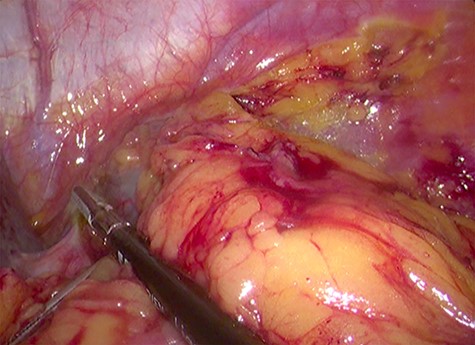

Because of its relatively large size and the patient’s request, he underwent a laparoscopic transperitoneal left adrenalectomy in the right lateral decubitus position (two 10-mm and one 5-mm ports). Intraoperatively, an enlarged left adrenal gland and a cystic lesion closely adherent to it were found, surrounded by adipose tissue (Figs 3 and 4). They were completely resected en bloc and removed in the endobag. No adverse events occurred postoperatively and he was discharged on Day 3.

Laparoscopic view of the retroperitoneal space containing the left adrenal gland and a cystic lesion surrounded by large amounts of adipose tissue.

Laparoscopic en bloc resection of the retroperitoneal cystic lesion adherent to the left adrenal gland and adipose tissue.